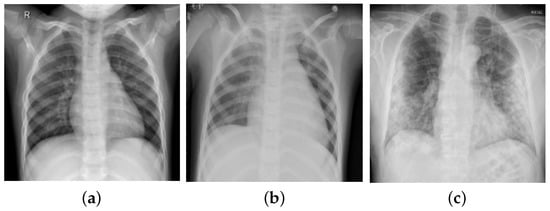

Image Enhancement: Image enhancement is frequently used in the biomedical image processing domain to improve image quality [38,39]. Therefore, in this study, we performed the image enhancement by employing bilinear interpolation (BI) followed by the contrast-limited adaptive histogram equalization (CLAHE) technique. Initially, BI was applied to replace the missing pixel by computing a weighted average of the nearest boundary pixels [40]. Then, CLAHE was employed for contrast enhancement that prevents over-enhancement of noise present in the images [41,42], thereby, facilitating better diagnosis. Figure 3 depicts the outcomes of the preprocessing stage (BI and CLAHE).

Figure 3.

Results of image enhancement (BI and CLAHE): (a–c) indicate original images, (d–f) indicate enhanced images.